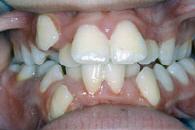

| Unterkiefervorlage | Unterkiefervorlage, frontoffen | |